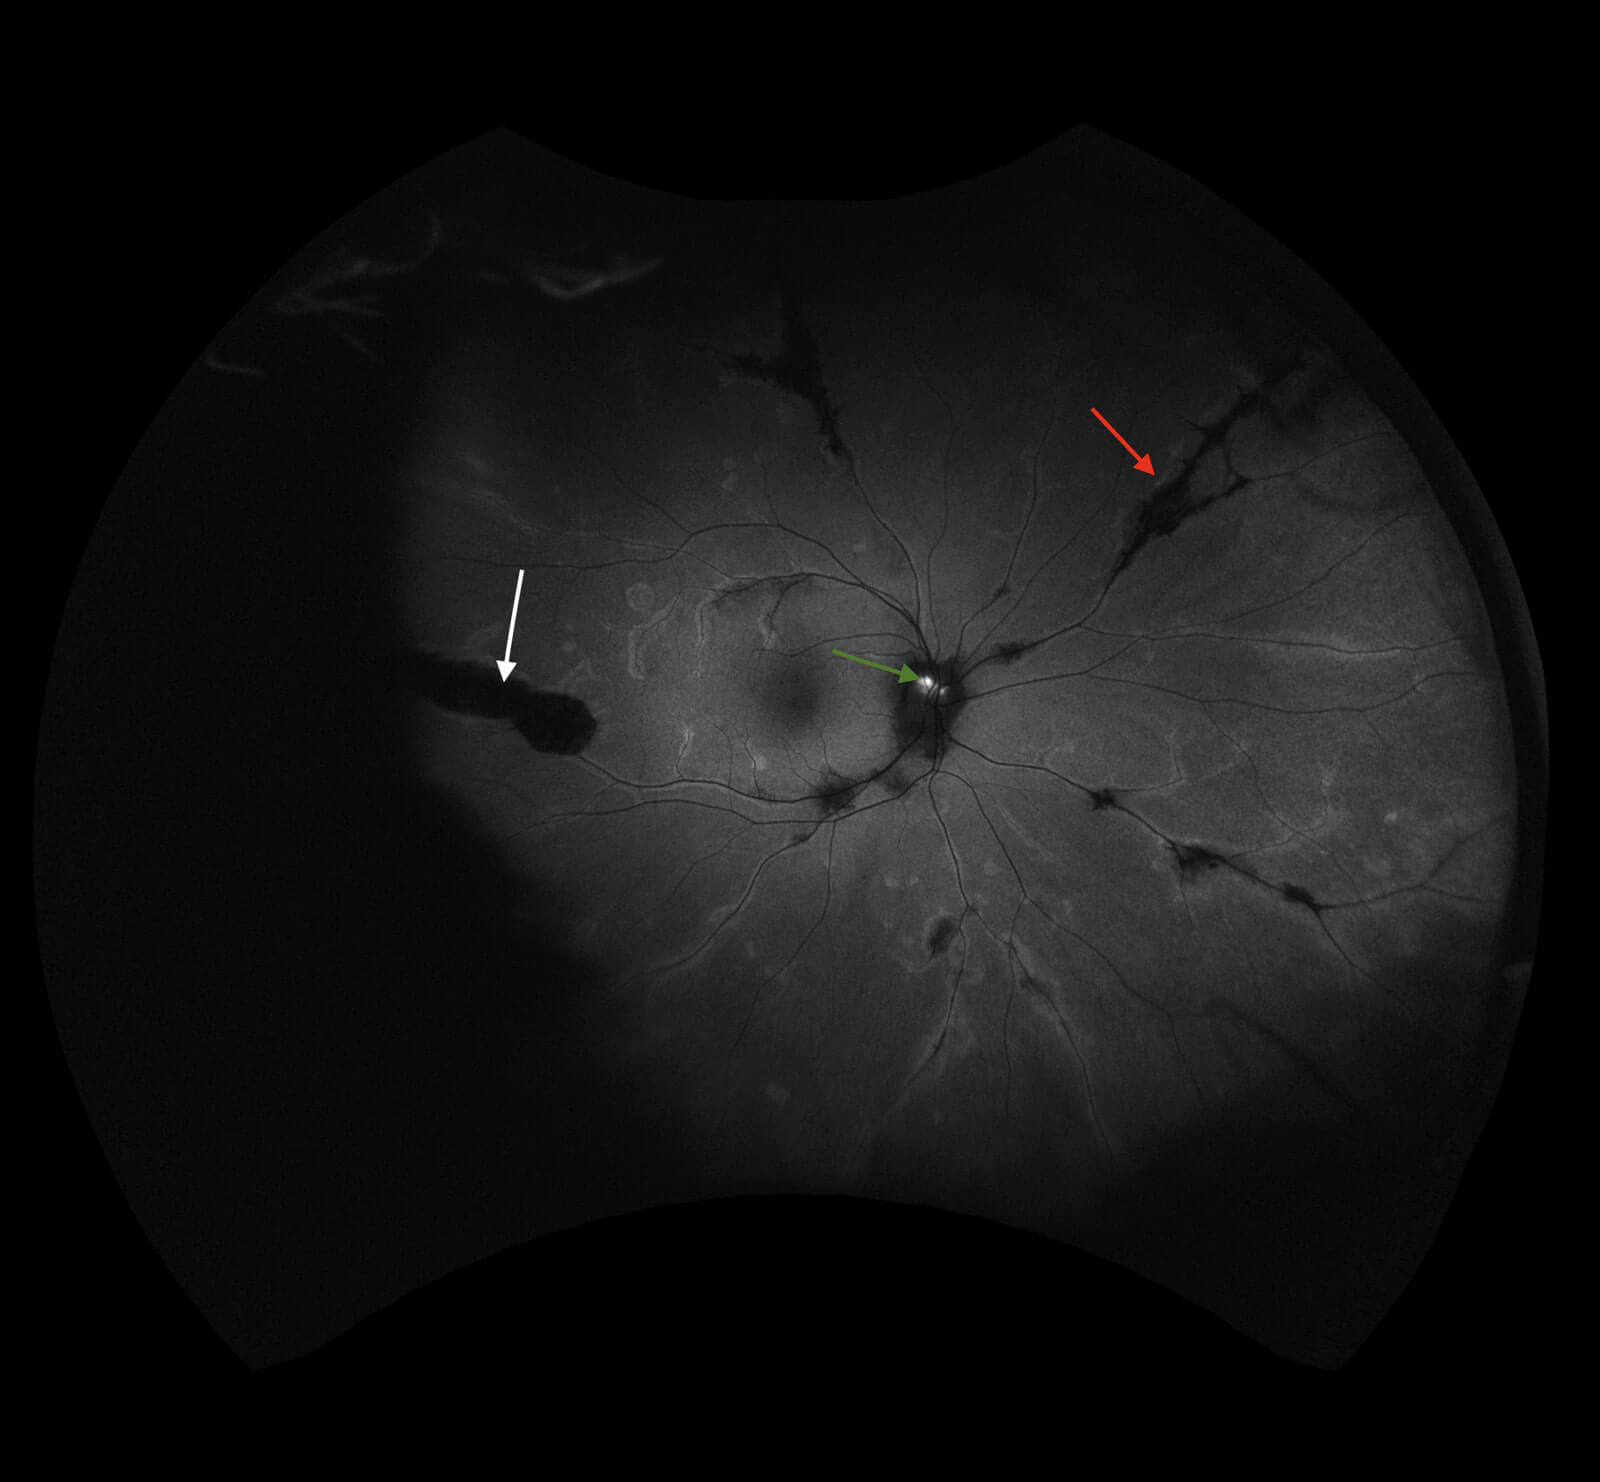

Widefield fundus imaging demonstrated these clinical findings (Figures 1a, 1b). Fundus autofluorescence showed hypo- autofluorescence in the areas of pigment accumulation and hyperautofluorescence in the areas of chorioretinal atrophy (Figures 2a, 2b). Fundus autofluorescence also showed hyper-autofluorescence at the optic disc indicative of optic nerve drusen. A 30-2 Humphrey visual field test revealed some defects superiorly paracentrally in the right eye. In the left eye there was a more significant field defect with an inferior and superior arcuate defect noted.

Figures 2a and 2b: Widefield fundus autofluorescence demonstrating hypo-autofluorescence in areas of pigment accumulation (white arrows), hyper-autofluorescence in areas of chorioretinal atrophy (red arrows) and hyper-autofluorescent optic nerve head drusen (green arrows).